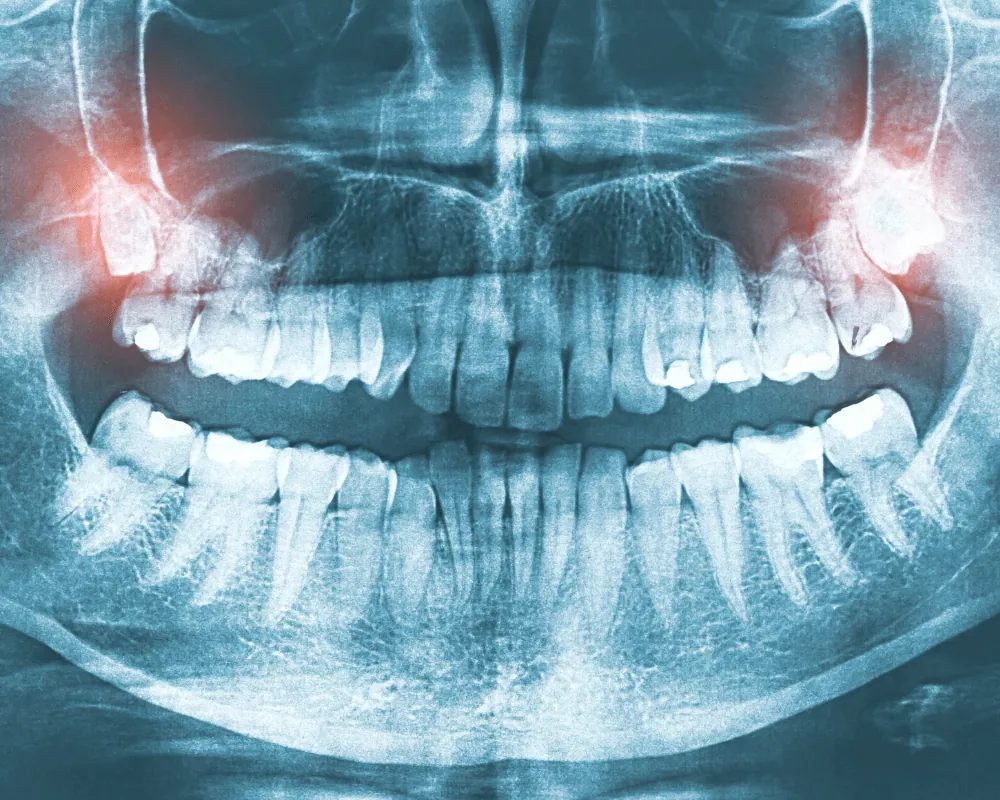

Ağız, Diş ve Çene Cerrahisi Nedir?

Ağız, diş ve çene cerrahisi, genel diş sağlığı ve cerrahi müdahaleleri içeren bir branştır. Bu alanda uzmanlaşmış olan Dentayeşilköy, çeşitli cerrahi prosedürlerle diş, çene ve ağız sağlığınızı en üst seviyede koruma amacını taşır.

2. Diş Çekimleri: Tedavi edilemeyen ya da gömülü kalmış dişlerin ağrısız ve kontrollü diş çekimleri.

3. Ortodontik Cerrahi: Çene düzensizliklerinin düzeltilmesi ve ortodontik cerrahi müdahaleler.